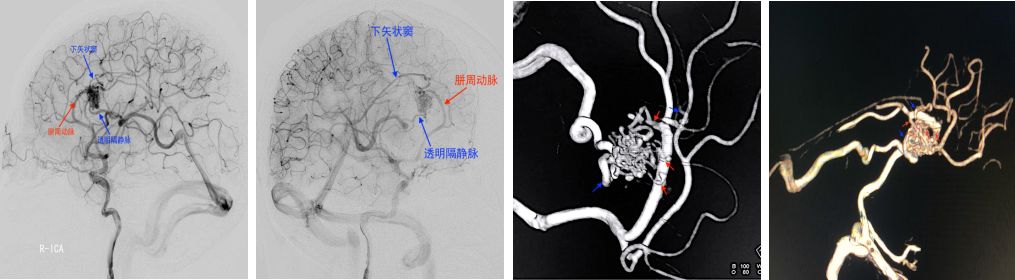

患者女性,39岁,以头痛1月余入院,患者入院前1个月无明显诱因出现头痛、头晕并呕吐,伴有短暂昏迷,当地医院头颅CT、MRI(图1),查体:未见异常。当地医院给予保守治疗,转入我院行DSA(图2)示:右侧胼胝体动静脉畸形。

图1:头颅CT:示脑室出血,头颅MRI:考虑右侧胼胝体动静脉畸形

图2:右侧颈内动脉造影,右侧胼胝体动静脉畸形,供血动脉为胼周动脉供应胼胝体动脉分支,引流静脉通过透明隔静脉向大脑内静脉引流及通过下矢状窦向直窦引流红色箭头为供血动脉,蓝色箭头为引流静脉。